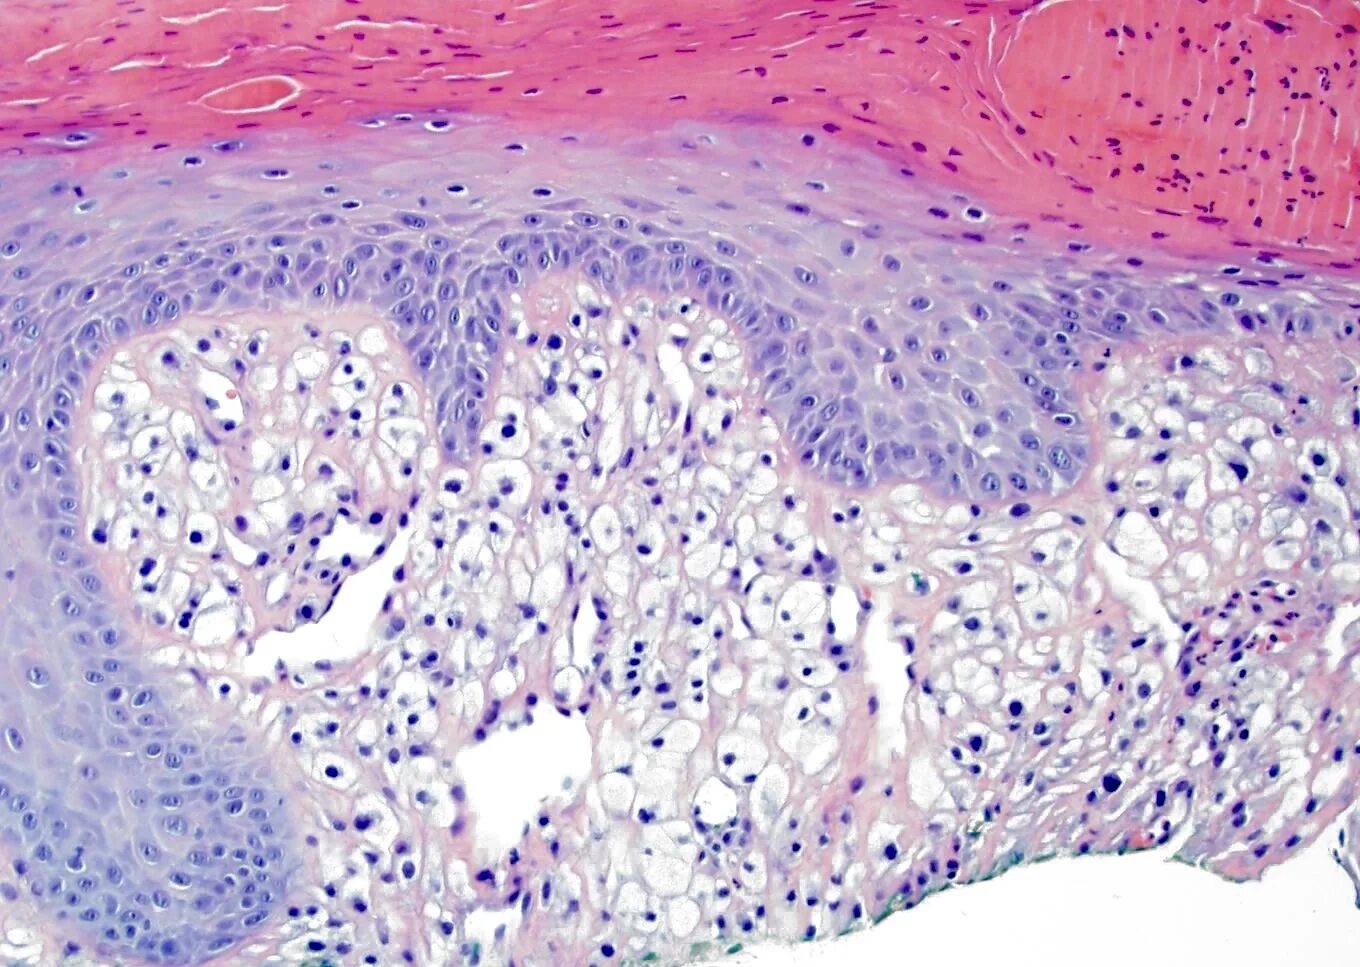

Гистология фото